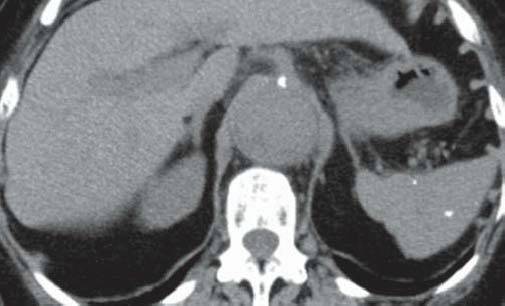

男性,48岁,以肺结节就诊。

A

B

图A和B为轴位CT平扫,示肝、脾内多发大小不一的钙化,肝、脾大小形态正常,图C和D为冠位重组纵隔窗及肺窗,示纵隔、肺门淋巴结钙化及肺的钙化结节,同时发现主动脉瘤。

组织胞楽菌病是美国中部的一种地方病,自艾滋病流行以来,本病发病率明显上升,在非流行地区也有报道。大多数组织胞浆菌病患者伴有纵隔淋巴结肿大、钙化(如本例所示),可引起纵隔压迫症状。患者腹部CT扫描可见散布的组织胞浆菌病,肝大(63%)、脾大(38%)、弥漫性脾密度减低(19%)、双侧肾上腺肿大、淋巴结肿大(44%)。在美国,治愈的组织胞浆菌荚膜感染是引起弥漫性脾钙化的最常见原因,引起多发脾钙化的其他原因有治愈的结核、布鲁杆菌病及肺囊虫感染、血管瘤、静脉石、含铁血黄素沉着症、镰状红细胞贫血和含铁结节(G-G小体)。